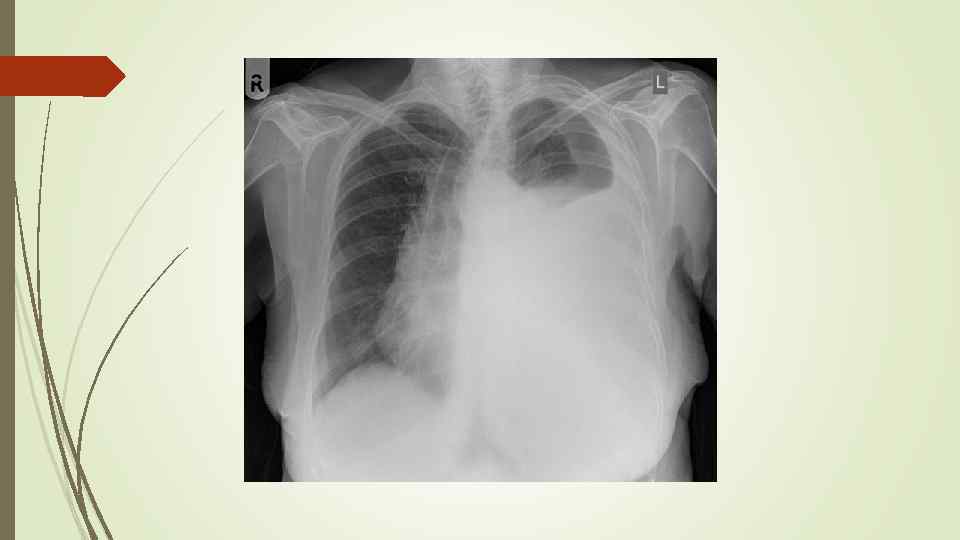

Бронхопневмония Характерно наличие двухсторонних множественных очаговых теней. Контуры очагов нечеткие, интенсивность тени небольшая. Инфильтрация неоднородна. Мелкие, малоинтенсивные очаги не всегда выявляются на снимках. Легочный рисунок усилен на всем протяжении легких. Корни расширены, не структурны. Как правило, отмечается реакция плевры, могут быть и экссудативные плевриты.

Бронхопневмония Характерно наличие двухсторонних множественных очаговых теней. Контуры очагов нечеткие, интенсивность тени небольшая. Инфильтрация неоднородна. Мелкие, малоинтенсивные очаги не всегда выявляются на снимках. Легочный рисунок усилен на всем протяжении легких. Корни расширены, не структурны. Как правило, отмечается реакция плевры, могут быть и экссудативные плевриты.

bronhopneumoni

bronhopneumoni

Плевральный выпот Скопление жидкости в плевральной полости (исключение гемоторакс, хилоторакс, пиоторакс) Транссудат Экссудат Плеврит

Плевральный выпот Скопление жидкости в плевральной полости (исключение гемоторакс, хилоторакс, пиоторакс) Транссудат Экссудат Плеврит

Пневмоторакс – скопление газа в плевральной полости, ведущее к спадению ткани легкого, смещению средостения в здоровую сторону, сдавлению кровеносных сосудов, опущению купола диафрагмы, что, в конечном итоге вызывает расстройство функции дыхания и кровообращения. Различают травматический, спонтанный и ятрогенный пневмоторакс. В зависимости от наличия связи с окружающей средой различают закрытый, открытый и клапанный пневмоторакс.

Пневмоторакс – скопление газа в плевральной полости, ведущее к спадению ткани легкого, смещению средостения в здоровую сторону, сдавлению кровеносных сосудов, опущению купола диафрагмы, что, в конечном итоге вызывает расстройство функции дыхания и кровообращения. Различают травматический, спонтанный и ятрогенный пневмоторакс. В зависимости от наличия связи с окружающей средой различают закрытый, открытый и клапанный пневмоторакс.

Рентгенологическое исследование: свободный газ в плевральной полости (участок просветления, лишенный легочного рисунка, расположенный на периферии легочного поля, на фоне пневмоторакса отчетливее, чем обычно, видны детали костного скелета грудной клетки) поджатое лёгкое, степень спадения которого зависит от величины пневмоторакса при напряжённом пневмотораксе средостение смещается в здоровую сторону.

Рентгенологическое исследование: свободный газ в плевральной полости (участок просветления, лишенный легочного рисунка, расположенный на периферии легочного поля, на фоне пневмоторакса отчетливее, чем обычно, видны детали костного скелета грудной клетки) поджатое лёгкое, степень спадения которого зависит от величины пневмоторакса при напряжённом пневмотораксе средостение смещается в здоровую сторону.